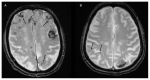

Intracerebral hemorrhage (ICH) accounts for 10% to 20% of all strokes worldwide and is associated with high morbidity and mortality. Neuroimaging is clinically important for the rapid diagnosis of ICH and underlying etiologies, but also for identification of ICH expansion, often as-sociated with an increased risk for poor outcome. In this context, rapid assessment of early hema-toma expansion risk is both an opportunity for therapeutic intervention and a potential hazard for hematoma evacuation surgery. In this review, we provide an overview of the current literature surrounding the use of multimodal neuroimaging of ICH for etiological diagnosis, prediction of early hematoma expansion, and prognostication of neurological outcome. Specifically, we discuss standard imaging using computed tomography, the value of different vascular imaging modalities to identify underlying causes and present recent advances in magnetic resonance imaging and computed tomography perfusion.